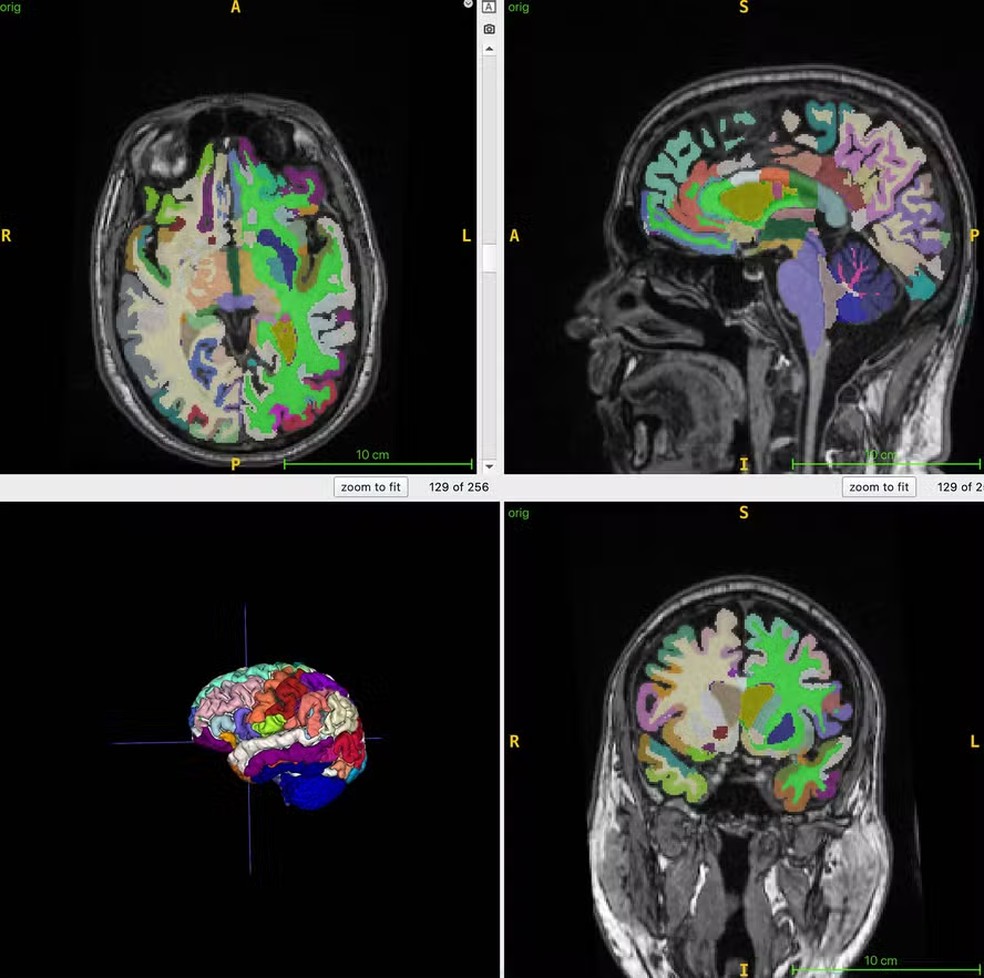

Imagens da figura do cérebro em cores na ressonância magnética usados para cálculos da idade cerebral — Foto: Cyrus Raji/ Sociedade Radiológica da América do Norte (RSNA)

A idade cerebral é a estimativa computacional da idade cronológica a partir de uma ressonância magnética estrutural do cérebro. A massa muscular, monitorada por ressonância magnética corporal, pode ser um marcador indireto para diversas intervenções que visam reduzir a fragilidade e melhorar a saúde cerebral, e a idade cerebral prevista por imagens estruturais do cérebro pode fornecer informações sobre fatores de risco para a doença de Alzheimer, como a perda muscular.

A idade cronológica média dos participantes era de 55,17 anos. Os pesquisadores combinaram imagens de RM com sequências ponderadas em T1, uma técnica que produz imagens onde a gordura aparece brilhante e o fluido aparece escuro. Isso permite a obtenção de imagens otimizadas de tecido muscular, adiposo e cerebral.

Um algoritmo de inteligência artificial (IA) foi utilizado para quantificar o volume muscular total normalizado, a gordura visceral (gordura abdominal oculta), a gordura subcutânea (gordura sob a pele) e a idade cerebral.